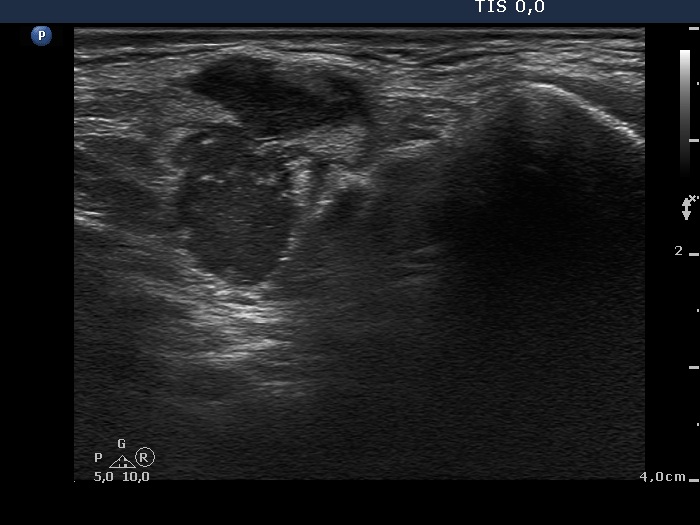

Ultrasonography: The thyroid was intact. There were multiple nodes in both supraclavicular regions. The nodes presented an absolutely irregular shape and border. They contained numerous hyperechogenic circumscribed areas.